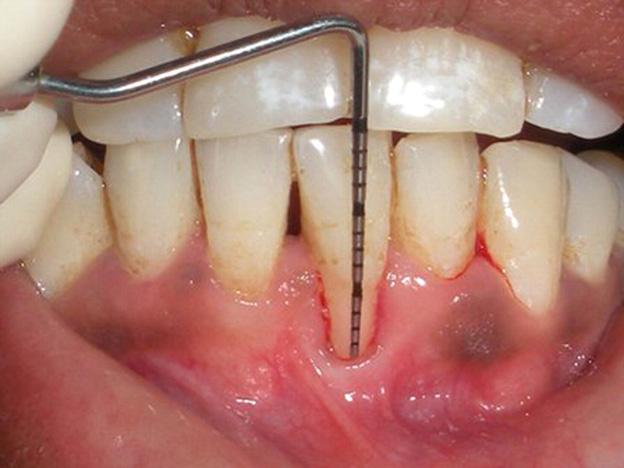

A routine dental examination can identify and uncover gum recession. The dentists will utilize a specialized instrument known as a periodontal probe to measure and assess the depth of periodontal pockets surrounding each tooth. Individuals with healthy gum have these pockets measured between 1 and 3 millimeters. Those with gingivitis may have these pockets at around 4 millimeters. However, those with periodontal disease may have pockets deeper than 5 millimeters. People with gum recession usually have accompanied bone loss.